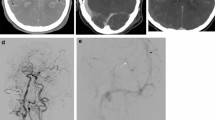

The definition of CVS in CTA was segmental vascular stenosis12, and postoperative TCD and CTA examination can exclude partial intracranial arterial stenosis patients (Fig. 2).

The definition of LAO in CTA was as follows: intracranial large artery-like middle cerebral artery (MCA, including M1 and M2), internal carotid artery (ICA), arterial cerebral artery (ACA), basilar artery (BA), vertebral artery (VA), etc., no image in CTA (Fig. 3). Additionally, to exclude chronic occlusion, the patient had no history or symptoms of ischemic stroke, the occluded side matched the trauma side, and the small blood vessels could not be seen on the CTA.

The definition of DVSO in CTA: intracranial deep venous systems such as basilar venous, Galen venous, and cerebral internal venous disappeared (Fig. 4).